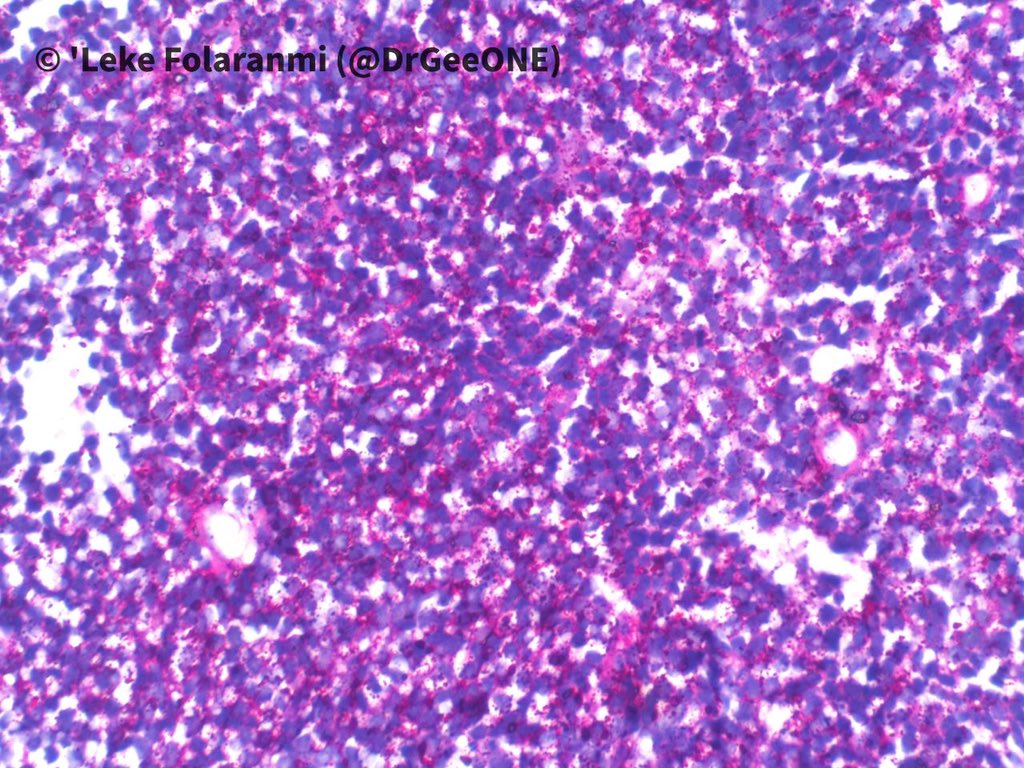

A male in his 20s with huge intrathoracic mass.

Duration: 2 years

❗️No IHC done

High power pictures of H/E and PAS sections